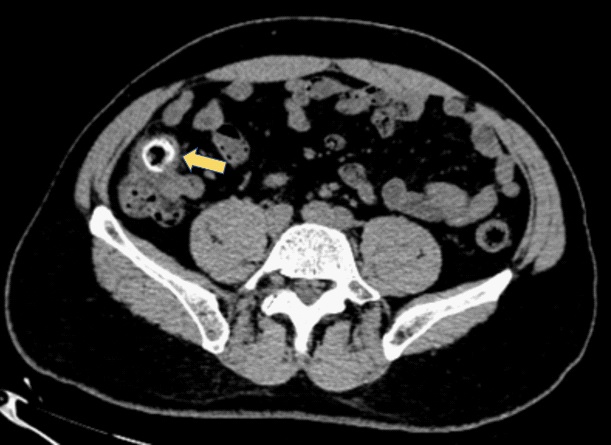

Figure 3: Colonoscopy showed the fecal impaction in the cecal diverticulum above the ileocecal valve.

The computed tomography scan of abdomen showed about 20 mm X 20 mm circular high density shadow in right colon, which can be observed in colonic lumen but protruding out of the lumen. Colonoscopy (Figure 3) was also performed and the fecal impaction was identified in the cecal diverticulum above the ileocecal valve. The mucosa surrounding the diverticulum was hyperemic and edema. Than the fecalith was removed successfully with a foreign forceps under colonoscopy. The internal mucosa of the diverticulum was hyperemia, and no perforation was observed (Figure 4). The patient’s abdominal pain were relieved after endoscopic treatment. To prevent recurrence of the disease, surgical removal of the diverticulum was recommended but the patient was hesitant. There was no recurrence of abdominal pain and fecal impaction during 10 months follow-up.